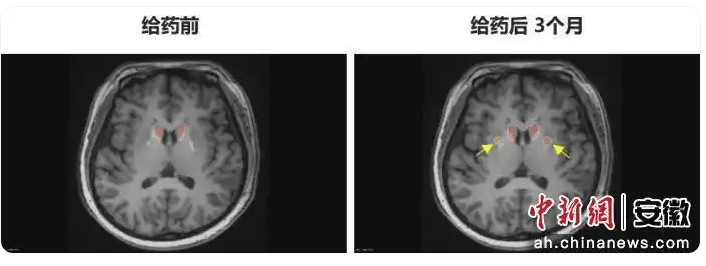

术后3个月的综合评估显示,患者各项功能指标均实现突破性改善。PET - DAT/MRI融合影像显示,移植细胞已在患者脑内成功定植并转化为功能性多巴胺能神经元,双侧纹状体形成显著的de novo新生多巴胺能活性成像,为功能性治愈提供了最直接的支撑。临床数据也直观地展现了治疗效果,患者运动功能得到根本性恢复,“关期”完全消失,每日“Good ON”(状态良好)时间增加4.5小时,提升近40%,且是否服用左旋多巴类药物已无明显差异。同时,患者生活质量全面回归,剂末现象、异动症等传统治疗难以解决的并发症彻底消失。